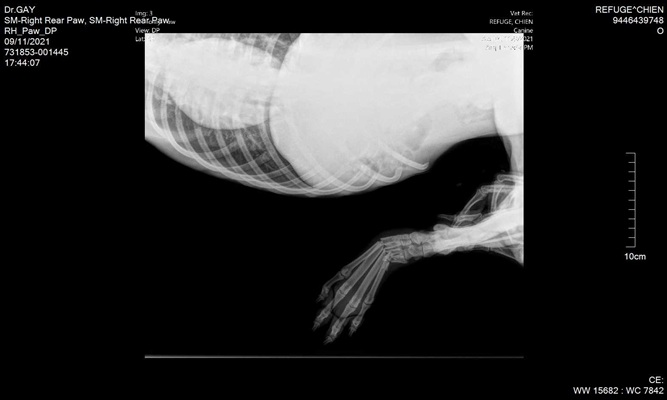

Unser Teenager BRADLEY ist erst ein Jahr jung und konnte dem Tod mit viel Glück gerade noch so entkommen. Er ist ein ORANGE Belton Rüde und ist einfach zum Knuddeln. Sein Jäger wollte ihn einschläfern lassen, da er sich die ersten Glieder seiner Zehen an der rechten Hinterpfote gebrochen hat. Er wird nun nächste Woche operiert und kann am 18. Dezember 2021 im Setterland auf sein Pflegestelle gehen.

Mittelfußfraktur - OP am 22.11.2021

BRADLEY ist ein wundervoller und liebevoller Rüde. Er ist Junghund typisch verspielt und kann es kaum erwarten eine Familie zu finden, die genügend Zeit und Geduld hat, ihm die große, weite Welt zu zeigen und zu erklären. Unser kleiner Elf hat einen Fersenbeinbruch, der operiert wurde. Er trägt zurzeit eine Schiene.